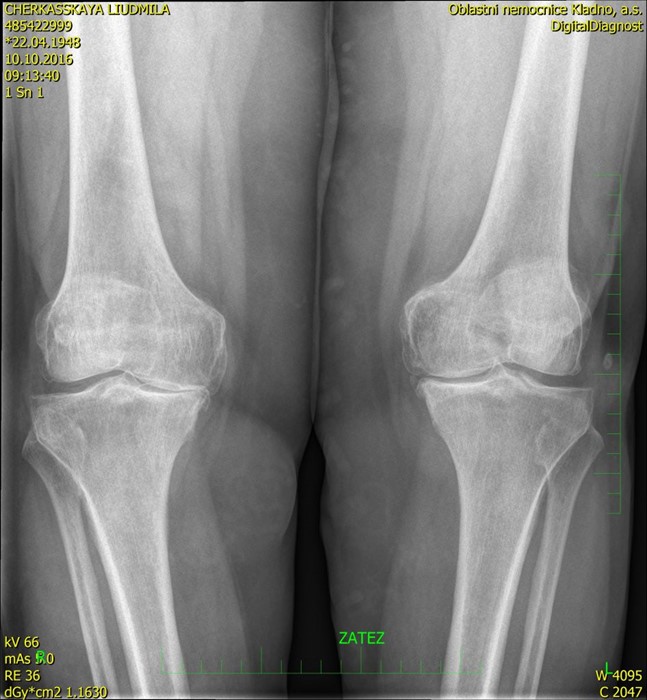

При данной патологии хрящ, который покрывает суставные поверхности костей, истончается и начинает расслаиваться, теряя свою прочность и эластичность. В результате разрушения хряща суставная щель значительно сужается, что приводит к патологическому трению между большеберцовой и бедренной костями. Это, в свою очередь, вызывает деформацию краев костных поверхностей, которые начинают расплющиваться, и образуются наросты (остеофиты). В конечном итоге возникают трудности со сгибанием и разгибанием конечности, развивается блокировка и нестабильность колена. Исправить такую ситуацию, кроме как с помощью операции по замене поврежденного коленного сустава, уже невозможно.

- деформирующий гонартроз;